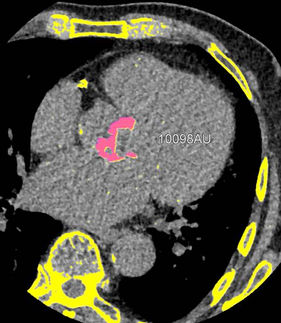

This online course provides a combination of didactic lectures and hands-on training on TAVI/TAVR CT planning and interpretation.

Learn how to use CT to measure aortic valve annulus, coronary heights, and evaluate access.

Aortic valve calcium scoring and interpretation.